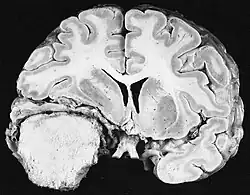

Im Tumorgewebe ist im Allgemeinen der größere Anteil der Kontrastverstärkung auf die besondere Blut-Tumor-Schranke zurückzuführen, die den Durchgang von Iod (CT) und Gadolinium (MRT) in den intratumoralen extravaskulären Interstitialraum ermöglicht. Dadurch steigt das Signal (Dichte oder Intensität) des Tumors. Es sollte jedoch darauf geachtet werden, dass die Kontrastverstärkung die Neoplasie von Periwundödemen nicht mit Sicherheit abgrenzt. Tatsächlich zeigt der anatomisch-pathologische Befund bei malignen infiltrierenden Gliomen Tumorgewebe, wie zum Beispiel beim Glioblastom und anaplastischem Astrozytom, auch jenseits des vasogenen Ödems, das durch die Zerstörung der Blut-Hirn-Schranke durch den Tumor verursacht wird. Letzterer klinischer Zustand ist durch diagnostische Bildgebung schlecht nachweisbar.[5][6]

Auf -Kernspintomogrammen erscheint ein intrakranieller Tumor als massive Läsion, die nach Verwendung des Kontrastmittels lumineszierender werden kann. Eine Signalanomalie gibt es jedoch immer in -Kernspintomogrammen, die auf das Vorhandensein einer Neoplasie oder eines vasogenen Ödems hinweist. Normalerweise ist eine stärkere Lumineszenz (Kontrastverstärkung) ein Hinweis auf einen Tumor höheren Malignitätsgrades. Ein Kontrastring ist charakteristisch für ein Glioblastom, wobei der Lumineszenzanteil dem lebenswichtigen Teil des bösartigen Tumors und der dunklere -hypointense Bereich der Gewebenekrose entspricht.[4]